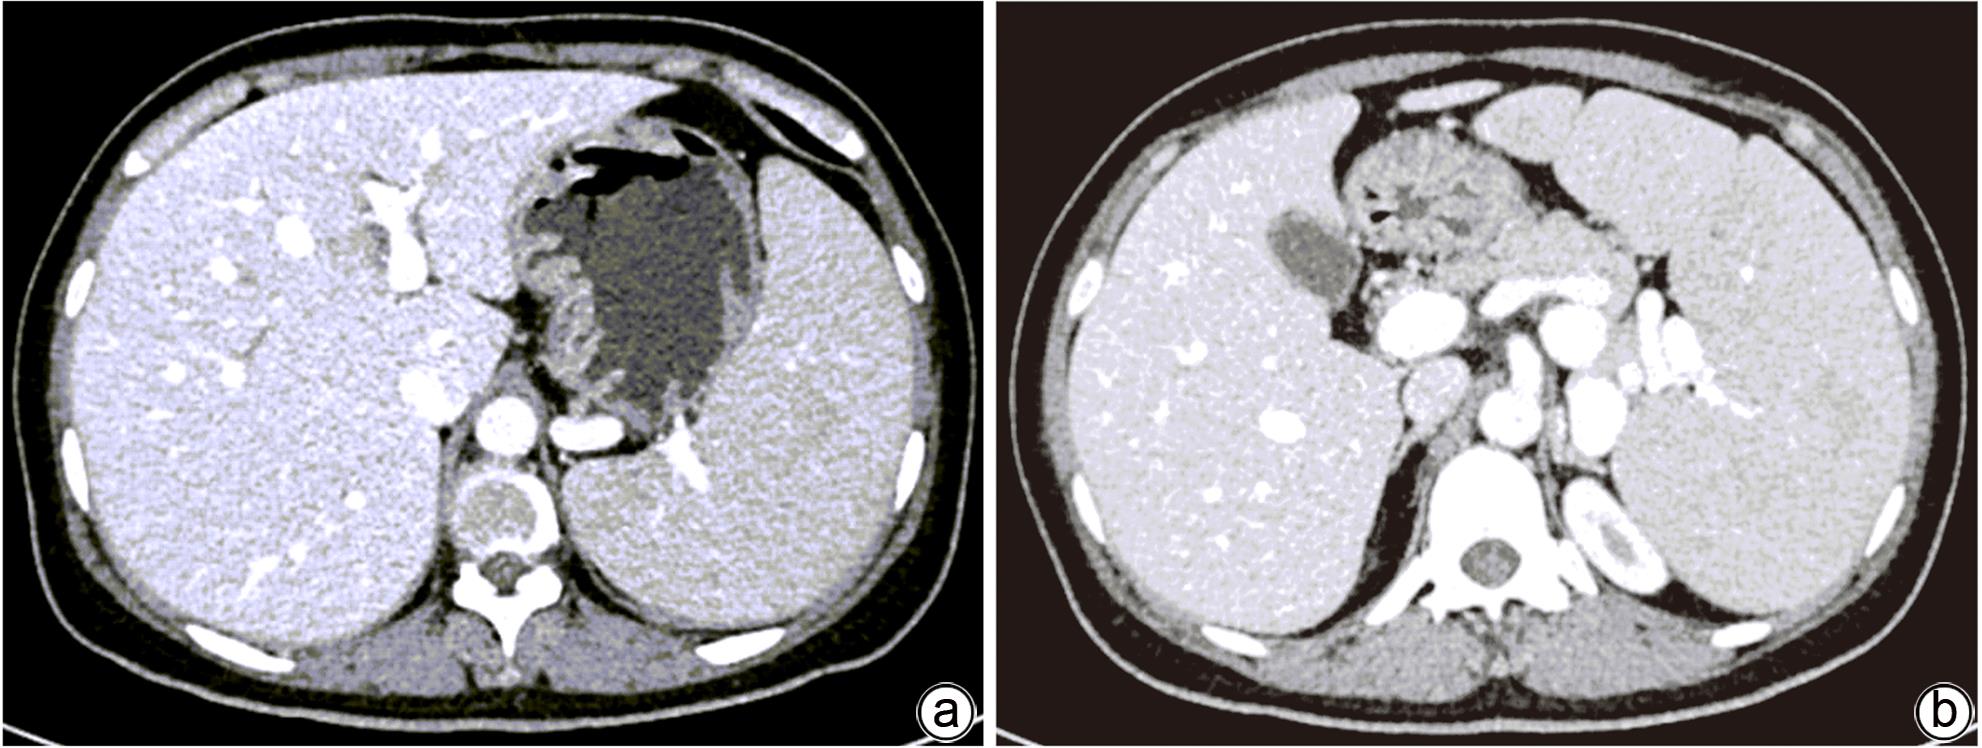

Misdiagnosis of intrapancreatic accessory spleen: A report of two cases

Mengzhe ZHANG, Jie RAO, Zhengle ZHANG

2024, 40(2): 365-368. DOI: 10.12449/JCH240223

Abstract(1274) HTML (315) PDF (1188KB)(59)

Abstract:

Accessory spleen refers to the spleen tissue that exists outside of the normal spleen, with a similar structure to the main spleen and certain functions. Intrapancreatic accessory spleen (IPAS) completely enveloped by the pancreas has an incidence rate of only 2%, and it is easily misdiagnosed in clinical practice due to its atypical clinical symptoms and similar radiological features to pancreatic neuroendocrine tumor, pancreatic solid pseudopapillary tumor, and other pancreatic space-occupying lesions. This article reports the clinical data of two patients with IPAS who were misdiagnosed as pancreatic neuroendocrine tumor and pancreatic solid pseudopapillary tumor, respectively, analyzes the reasons for misdiagnosis, and summarizes the experience in diagnosis and treatment, in order to improve the ability for the differential diagnosis of IPAS in clinical practice.